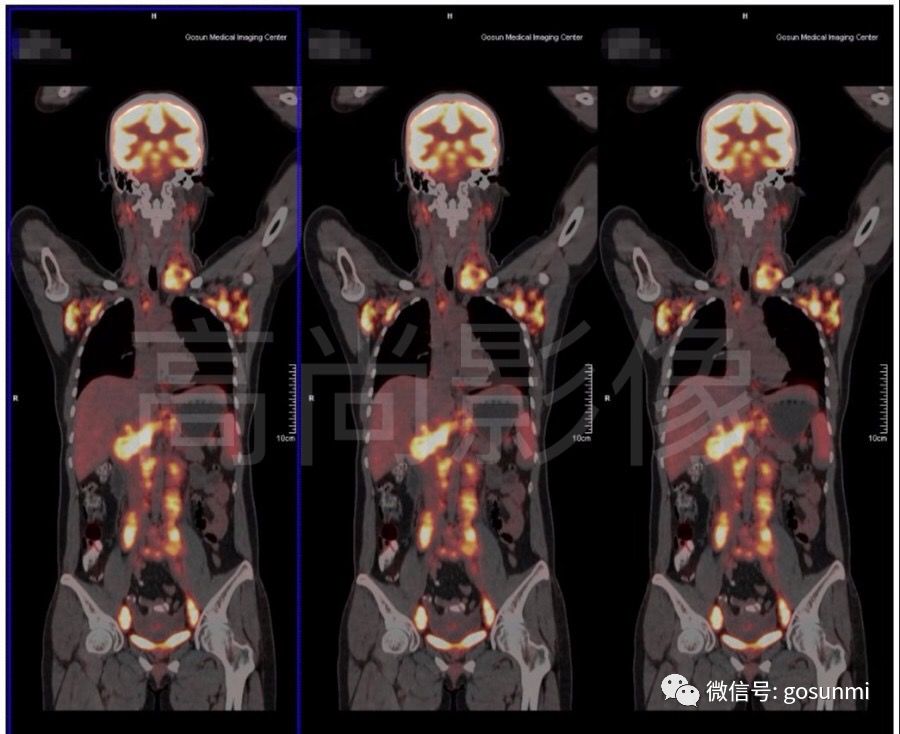

二、淋巴瘤的病變非常廣泛,常常不能準(zhǔn)確判斷有淋巴結(jié)腫大的部位是否真的有腫瘤的累及。對(duì)于頸部和盆腔的淋巴結(jié)有異常高代謝病灶的情況,PET/CT能夠清楚顯示。因此對(duì)于惡性淋巴瘤的患者,尤其是還沒有開始治療的患者,PET/CT可以更加準(zhǔn)確的判斷腫瘤的范圍,有利于明確臨床分期和制定治療計(jì)劃。

(淋巴瘤化療前)

(淋巴瘤化療后)

三、PET/CT對(duì)于惡性淋巴瘤的治療評(píng)價(jià)有重要作用。在痛苦的數(shù)個(gè)療程化療后,體內(nèi)殘留的淋巴結(jié)或淋巴組織是殘留病灶、壞死組織還是纖維組織?這是每位患者及醫(yī)生最關(guān)心的問題,由于PET/CT能夠顯示組織的代謝活性,因此具有比普通CT 具有更好的分辨能力,它能對(duì)影像學(xué)外觀相似的組織進(jìn)行鑒別,以辨別是否還有腫瘤組織或細(xì)胞存活。